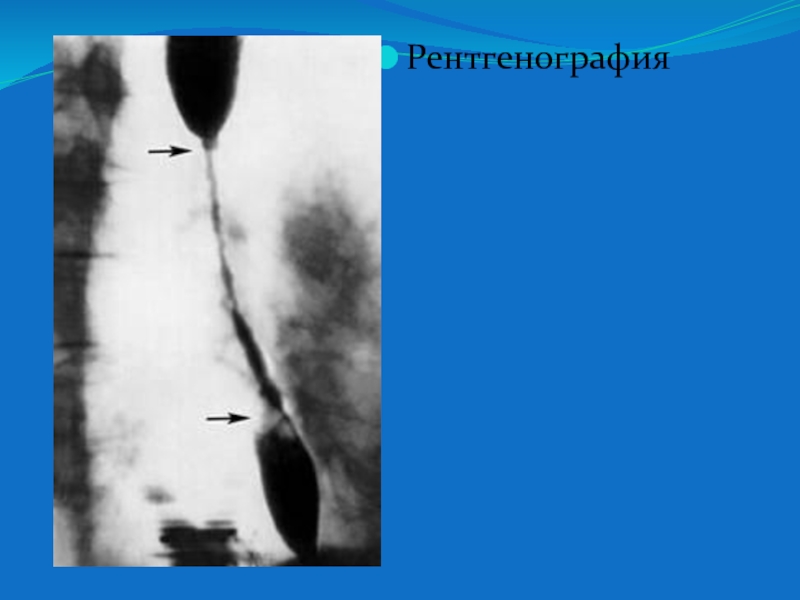

Слайд 11Рентгенография

Рентгенография

Слайд 12Контрастная R- графия пищевода - при исследовании пищевода отмечается его

значительное сужение на протяжении средней и нижней трети, стенки ровные,

перистальтика усилена.

Учитывая результаты R- графии пищевода ФГДС проводить не стали.